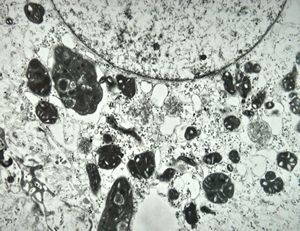

F,7m. | giant cell hepatitis